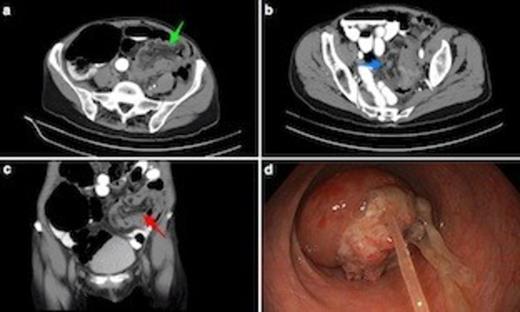

(a) Axial CT scan shows sigmoidorectal intussusception. Note bowel wall thickening. Low attenuation mesenteric tissue is drawn into intussusceptum, with associated caecal dilatation. (b) Axial view through mid-pelvis showing gas between bowel wall of intussusceptum and intussucipiens (i.e. sigmoid colon and rectum: this does not represent intramural gas). (c) Coronal view demonstrating mesenteric vasculature in the intussusceptum. (d) Endoscopic view from mid rectum of tumour intussusception. The underlying lesion was an apple core T3N1 adenocarcinoma of the mid-sigmoid. Note tumour mucus.

Subsequent CT scan revealed a rounded heterogeneous density protruding into the lumen of the upper rectum containing mesenteric fat and blood vessels (Figs. 1a-c). The appearance was suggestive of sigmoidorectal intussusception. There was significant associated proximal large bowel dilatation consistent with left-sided colonic obstruction.

The patient proceeded to emergency surgery. On the operating table, flexible sigmoidoscopy confirmed the diagnosis of intussusception due to a sigmoidal tumour (Fig. 1d). At laparotomy, a mass in the mid sigmoid colon was found with intussusception of the tumour into the rectum. A Hartmann’s procedure was performed. Post-operative recovery was complicated by rapid atrial fibrillation, but was otherwise uneventful. The patient was discharged home nine days after surgery. Histopathology of the surgical specimen showed a T3N1 moderately differentiated colonic adenocarcinoma.